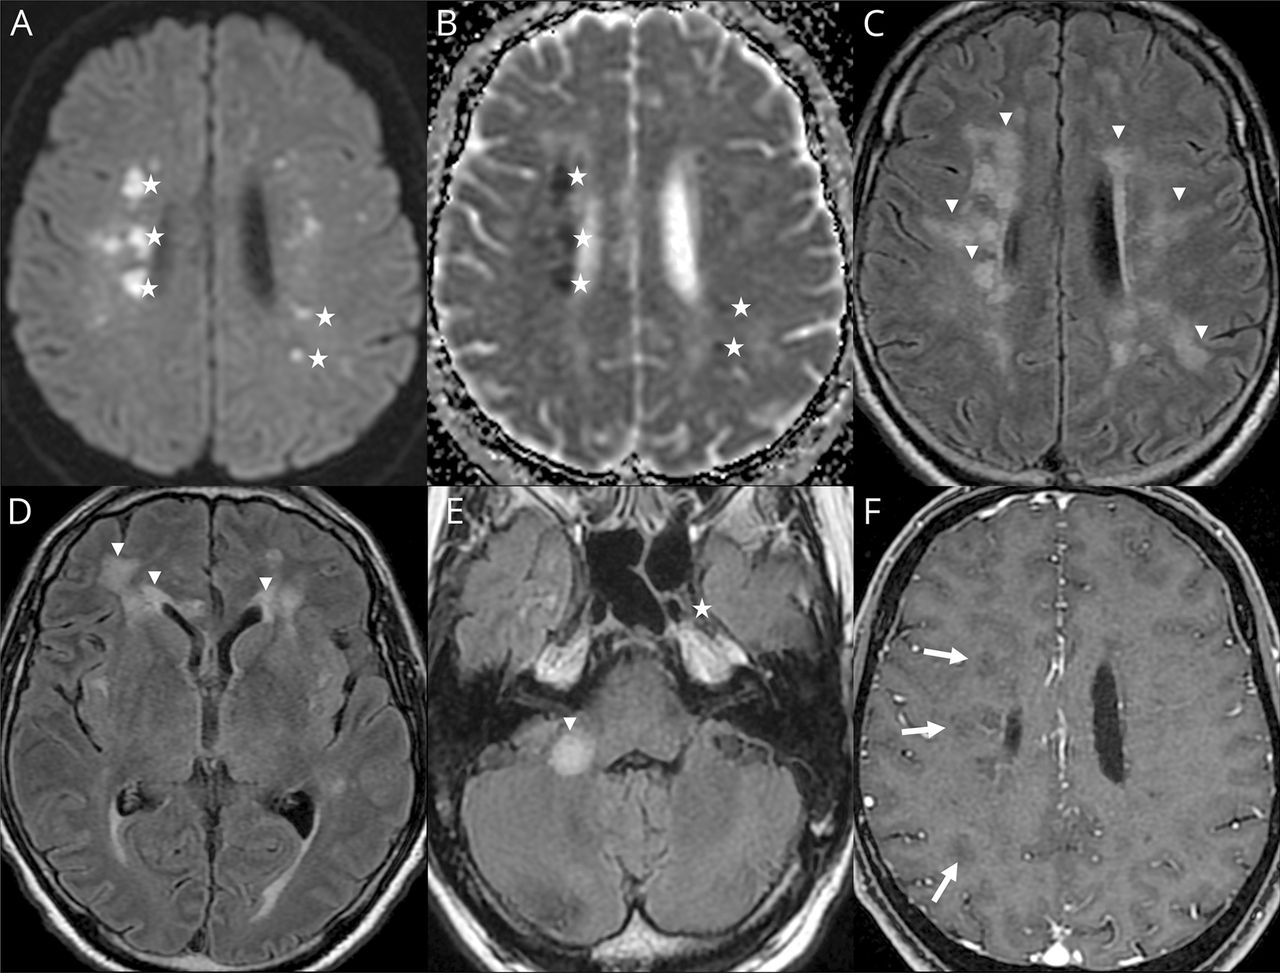

Ischemic strokes (27%) (figure e-1, available from Dryad,doi.org/10.5061/dryad.w9ghx3fm7), LME (17%) (figure 1), and encephalitis (13%) (figures 2and3and figure e-2, available from Dryad) were the most frequent neuroimaging findings. LME was seen on both postcontrast T1-weighted and FLAIR sequences and was even better visualized when delayed postcontrast FLAIR was performed. These signal abnormalities were not present on precontrast T1 or FLAIR images.

(A, B, D) Axial fluid-attenuated inversion recovery (FLAIR) and (C) diffusion-weighted MRIs. (A) Man 56 years of age: left hippocampus and amygdala FLAIR hyperintensity. (B) Woman 71 years of age: periventricular and subcortical white matter FLAIR confluent hyperintensities. (C) Man 55 years of age: corpus callosum splenium diffusion hyperintensity. (D) Man 64 years of age: FLAIR middle cerebellar peduncle hyperintensity.

(A, E, I) Axial fluid-attenuated inversion recovery (FLAIR), (B, F, J) axial diffusion, (B, F, J) apparent diffusion coefficient (ADC) map, and (D, H, L) postcontrast T1-weighted MRIs. Man 60 years of age: subcortical, periventricular, corpus callosum, and posterior fossa white matter FLAIR hyperintensities without contrast enhancement (arrows). Some lesions appear hyperintense on diffusion-weighted MRIs, with decreased ADC corresponding to cytotoxic edema (stars). Other lesions present an ADC increase corresponding to vasogenic edema (cross).

Among the 8 encephalitis, 2 cases of limbic encephalitis, 2 cases of radiologic acute hemorrhagic necrotizing encephalopathy, 2 cases of miscellaneous encephalitis, 1 case of radiologic ADEM, and 1 case of CLOCC were described.